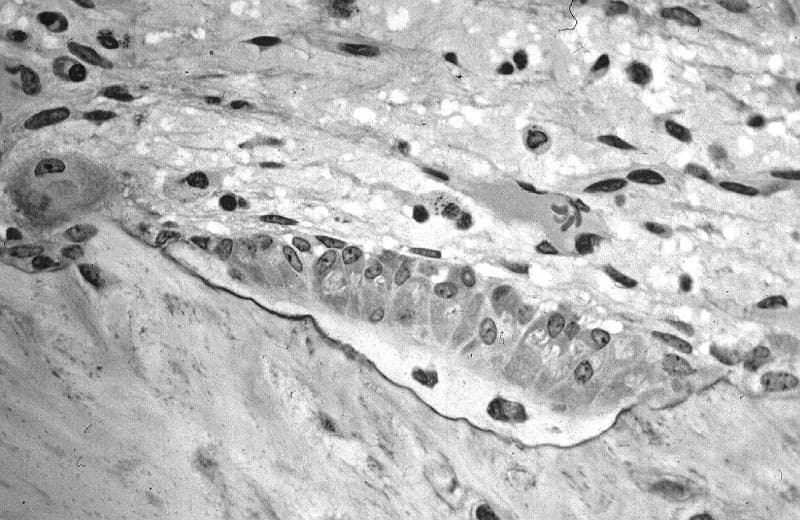

In histology, osteoid is the unmineralized, organic portion of the bone matrix that forms prior to the maturation of bone tissue. Osteoblasts begin the process of forming bone tissue by secreting the osteoid as several specific proteins. When the osteoid becomes mineralized, it and the adjacent bone cells have developed into new bone tissue. Osteoid makes up about fifty percent of bone volume and forty percent of bone weight. It is composed of fibers and ground substance. The predominant type of fiber is type I collagen and comprises ninety percent of the osteoid. The ground substance is mostly made up of chondroitin sulfate and osteocalcin. When there is insufficient nutrient minerals or osteoblast dysfunction, the osteoid does not mineralize properly, and it accumulates. The resultant disorder is termed rickets in children and osteomalacia in adults. A deficiency of type I collagen, such as in osteogenesis imperfecta, also leads to defective osteoid and brittle, fracture-prone bones. In some cases, secondary hyperparathyroidism can cause disturbance in mineralisation of calcium and phosphate. Another condition is a disturbance in primitive transformed cells of mesenchymal origin which exhibit osteoblastic differentiation and produce malignant osteoid. This results in the formation of a malignant primary bone tumor known as osteosarcoma or osteogenic sarcoma. This malignancy most often develops in adolescence during periods of rapid osteoid formation (commonly referred to as growth spurts).